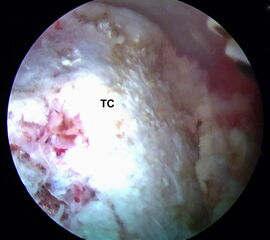

Abbildungen 14-17, Videos 4-5

Im nächsten Schritt erfolgt die arthroskopische Darstellung des Tuber calcanei (TC) mit Hilfe des Weichteilshavers und der Radiofrequenzsonde, bis eine gute Übersicht über die knöchernen Strukturen gegeben ist. Damit eine einwandfreie Orientierung und Platzierung des Zielgeräts gewährleistet ist, müssen alle störenden Gewebereste vollständig am Tuber entfernt werden. Zur besseren Übersicht kann es ggf. erforderlich sein, zusätzlich die tiefen paraachillären Zugänge zu verwenden (siehe oben). Unter arthroskopischer Sicht wird der Zielbügel über das posteromediale Portal eingeführt und auf der kranialen Prominenz des Tuber calcanei (TC) platziert. Arastru et al. 15 konnten in biomechanischen Untersuchungen am Kadaver nachweisen, dass die Fixation der FHL-Sehne möglichst weit posterior am Kalkaneus zu einem günstigen Hebelarm mit der besten Kraftentwicklung in der Plantarflexion führt.